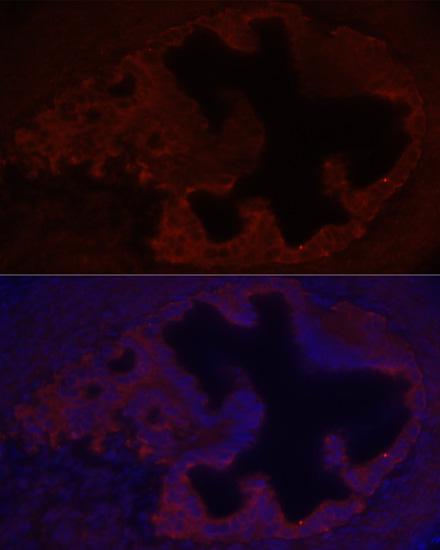

Immunofluorescence analysis of rat ovary using COL1A1 at dilution of 1:100. Blue: DAPI for nuclear staining.

Immunofluorescence analysis of human breast cancer using COL1A1 at dilution of 1:100. Blue: DAPI for nuclear staining.

Immunofluorescence analysis of human breast cancer using COL1A1 at dilution of 1:100. Blue: DAPI for nuclear staining.